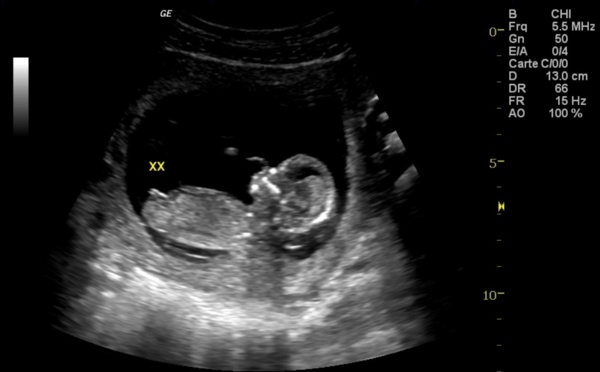

Une colombienne de 82 ans vivait avec un fœtus de 40 ans

Une Colombienne âgée de 82 ans souffrait de fortes douleurs à l'estomac. Les médecins pensaient d'abord qu'il s'agissait de calculs biliaires. Après une échographie poussée, il s'est avéré que cette dame portait un foetus vieux de 40 ans dans son ventre. Le foetus, qui est aujourd'hui un ensemble de tissus morts, s'est...